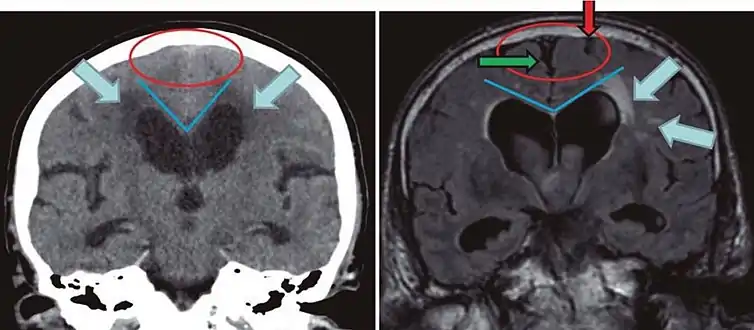

Cerebral atrophy can be hard to distinguish from hydrocephalus because both cerebral atrophy and hydrocephalus involve an increase in cerebrospinal fluid (CSF) volume. In cerebral atrophy, this increase in CSF volume comes as a result of the decrease in cortical volume. In hydrocephalus, the increase in volume happens due to the CSF itself.[20]

Typical imaging findings in normal pressure hydrocephalus versus brain atrophy.[21]

Normal pressure hydrocephalusBrain atrophy

Preferable projectionCoronal plane at the level of the posterior commissure of the brain.

Modality in this exampleCTMRI

CSF spaces over the convexity near the vertex (red ellipse )Narrowed convexity ("tight convexity") as well as medial cisternsWidened vertex (red arrow) and medial cisterns (green arrow)

Callosal angle (blue V)Acute angleObtuse angle

Most likely cause of leucoaraiosis (periventricular signal alterations, blue arrows ) Transependymal cerebrospinal fluid diapedesis Vascular encephalopathy, in this case suggested by unilateral occurrence